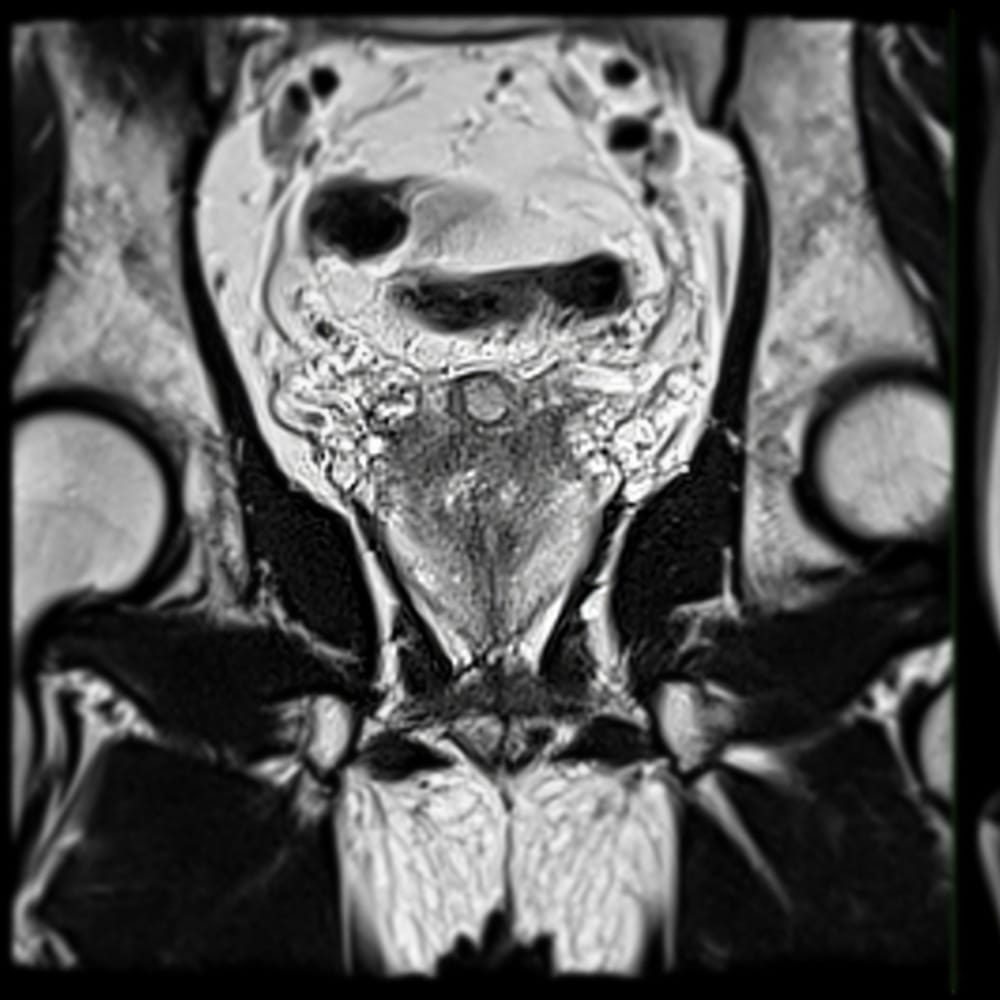

Prostate MRI Screening Scan

Our Prostate MRI Screening scan uses an exclusive 3T MRI scanner to provide high-resolution imaging of the prostate gland for cancer without radiation or contrast. It is comfortable study without rectal probe or coils & is non-invasive designed to support early detection of prostate cancer. This is a private-self-pay service and is not covered by OHIP.

Prostate MRI

High Resolution 3T Imaging

Dedicated prostate protocol on a 3T MRI scanner for detailed images